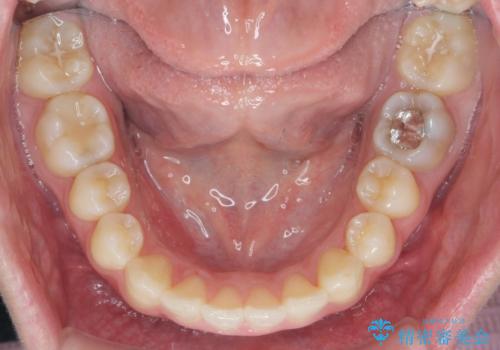

前歯の角度だけでなく内側に倒れ込んでいた奥歯もしっかり起こすことで咬合関係も理想的に仕上げています。